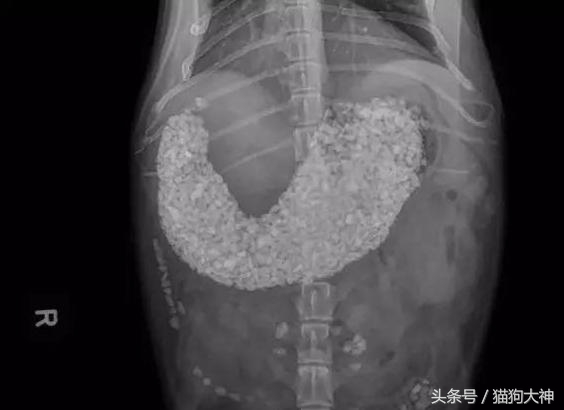

这是一只12岁柯基的胃,由于患上的异食癖,吃了一堆家里盆栽里的土和小石子,把胃都塞满了。这不是一天两天造成的,吃下一堆不能消化的东西狗狗一般会食欲不振,没有精神或排泄困难等表现,如果主人早点注意到,就不会这么严重了。